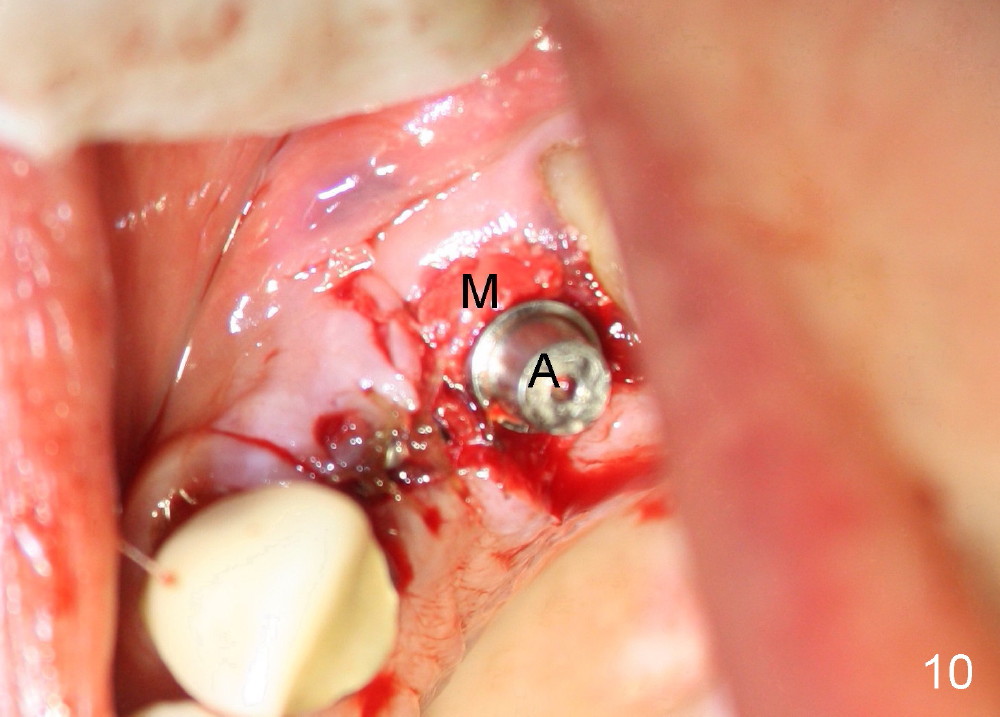

The anterior retainer is kept as a crown at #11 (Fig.2: C), whereas the residual root at the site of #13 is extracted with apical perforation (Fig.3 ^).  It is confirmed by Fig.4 (<).  To close the perforation, an osteotomy is initiated on the palatal wall of the socket with a 2 mm osteotome (Fig.5 insert: circle).  As the osteotomy is being enlarged by a 3 mm osteotome, the bone between the original socket and the osteotomy is being pushed buccally.  The former is being closed (Fig.5).  The osteotomy is finished with combination of osteotomes and reamers.  Fig.6 shows that a 5x14 mm tap is inserted at the site of #13 and that the sinus floor is lifted.  In fact the sinus membrane is partially torn at the osteotomy, which is repaired by insertion of Colla-form Dressing (Impladent), followed by autogenous bone (harvested from reamers) mixed with Osteogen  (Impladent).  A 5x14 mm implant is placed at the site of #13 with insertion torque more than 60 Ncm (Fig.7: I).  An incision is made at the site of #12 to start osteotomy with insertion of a parallel pin (Fig.7 P).  A 3 mm reamer is kept in place for position confirmation (Fig.8 R).  Due to ridge atrophy (Fig.2 arrowheads), a much smaller, but longer implant is placed at the site of #12 (Fig.9: 4x17 mm).  The autogenous bone harvested from #12 osteotomy is placed in the buccal gap of #13, followed by insertion of Colla-form Dressing (Fig.10 M).  To protect the membrane, a short abutment (4x3 mm) is temporarily placed (Fig.9,10 A) and perio dressing (Fig.9 D) is applied around the abutment and the interproximal areas of the neighboring teeth.  Usually perio dressing dislodges around 1 week postop, particularly for a large edentulous space.  In this case, the dressing is quite stable 11 days postop: the abutment (Fig.11 A) appears to contribute to retention of the dressing (D).